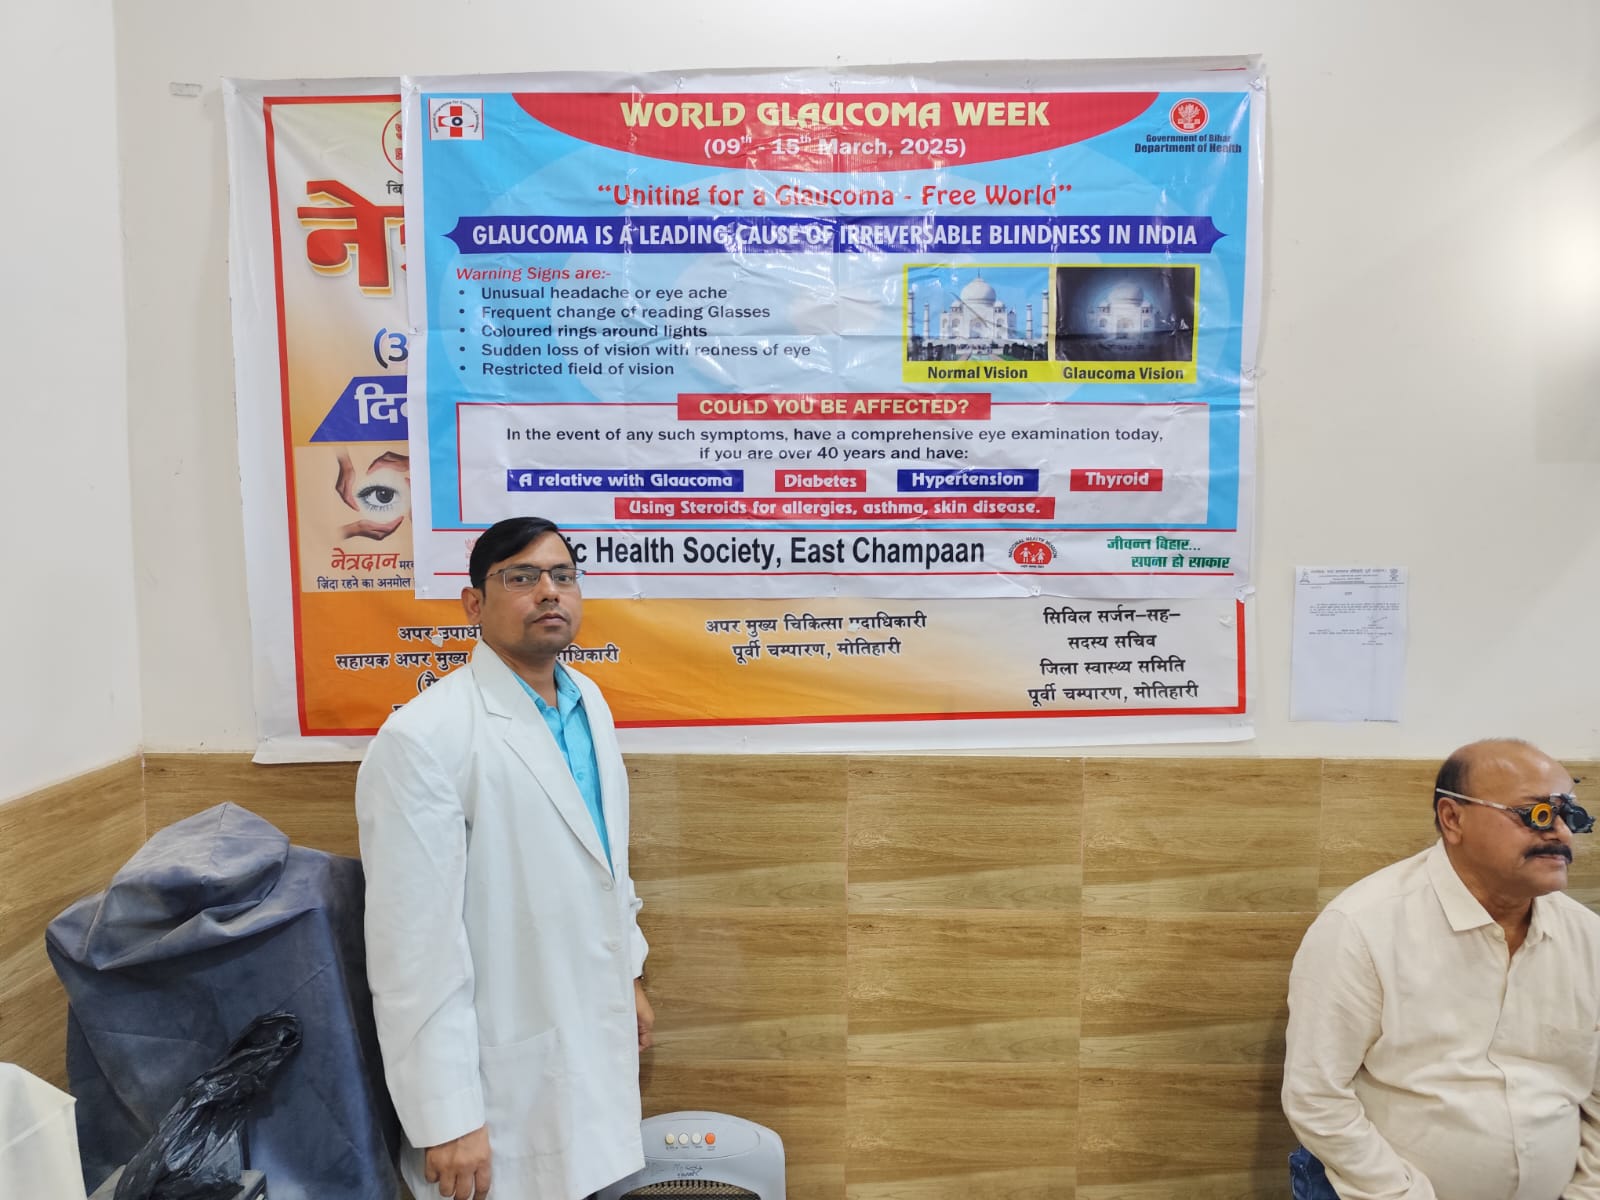

Kunti Netralaya, led by Dr. Dhananjay Prasad (MBBS, MS – DMCH Darbhanga), is dedicated to providing advanced, ethical, and affordable eye care to every patient. With experience as Ex-Consultant (IGEHRC Amethi), Ex–Senior Resident (NMCH Patna), and Visiting Eye Surgeon (Ramakrishna Mission, Muzaffarpur), Dr. Prasad combines expertise and compassion to deliver the best outcomes. Our goal is to ensure clear vision and lasting eye health for every patient.